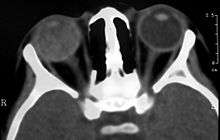

Computed Tomography image of a patient with Coats' disease, showing total exudative retinal detachment in the right eye.

Imaging studies such as ultrasonography (US), Computerized Tomography (CT) and Magnetic Resonance Imaging (MRI) can aid diagnosis. On ultrasound, Coats' disease appears as a hyperechoic mass in the posterior vitreous without posterior acoustic shadowing; vitreous and subretinal hemorrhage may often be observed.[6][7]

On CT, the globe appears hyperdense compared to normal vitreous due to the proteinaceous exudate, which may obliterate the vitreous space in advanced disease. The anterior margin of the subretinal exudate enhances with contrast. Since the retina is fixed posteriorly at the optic disc, this enhancement has a V-shaped configuration.[2]